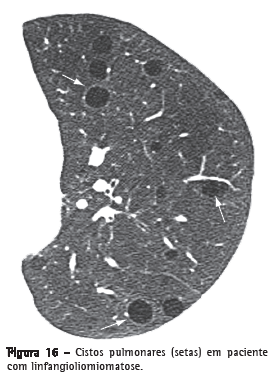

CistoCisto é qualquer espaço arredondado, bem circunscrito, que é circundado por uma parede epitelizada ou fibrosa, de espessura variável.(29) Na TC, caracteriza-se por uma área arredondada de baixo coeficiente de atenuação no parênquima pulmonar com uma interface bem definida com o pulmão normal adjacente (Figura 16).(1,7) A espessura da parede do cisto pode variar, sendo normalmente fina (< 2 mm). Cistos geralmente contêm ar, mas, ocasionalmente, podem conter líquido (por ex.: cisto broncogênico) ou mesmo algum material sólido. Doenças que cursam geralmente com múltiplos cistos pulmonares incluem a linfangioliomiomatose, a histiocitose de células de Langerhans, a pneumonia intersticial linfocítica e a síndrome de Birt-Hogg-Dubé.(30,31)